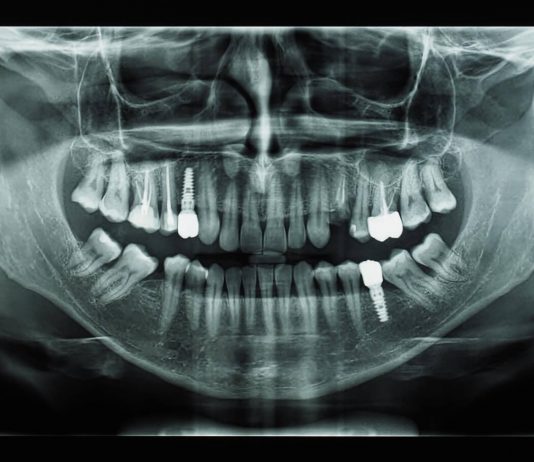

Имплантация зубов – это современная стоматологическая операция, представляющая собой установку искусственного корня на место отсутствующего зуба. С помощью имплантатов проводят протезирование зубов, которое позволяет восстановить функции и эстетику улыбки.

Клиника «SmileClinic» проводит ИМПЛАНТАЦИЮ ЗУБОВ тут https://smilespb.ru/uslugi/implantatsia_zubov_pod_kluch/ с применением самых передовых технологий. Также это оборудование позволяет сделать их максимально комфортными для...